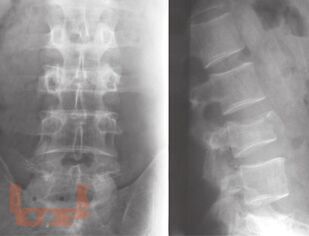

В настоящих методических рекомендациях обобщены научные данные и личный профессиональный опыт организации рентгеновской службы, описаны методы лучевой диагностики. Освещаются методы исследования органов и систем человека с нормальной анатомией, эмбриогенезом, рентгеноанатомией, а также рентгеносемиотика различных патологических состояний у взрослых и детей.